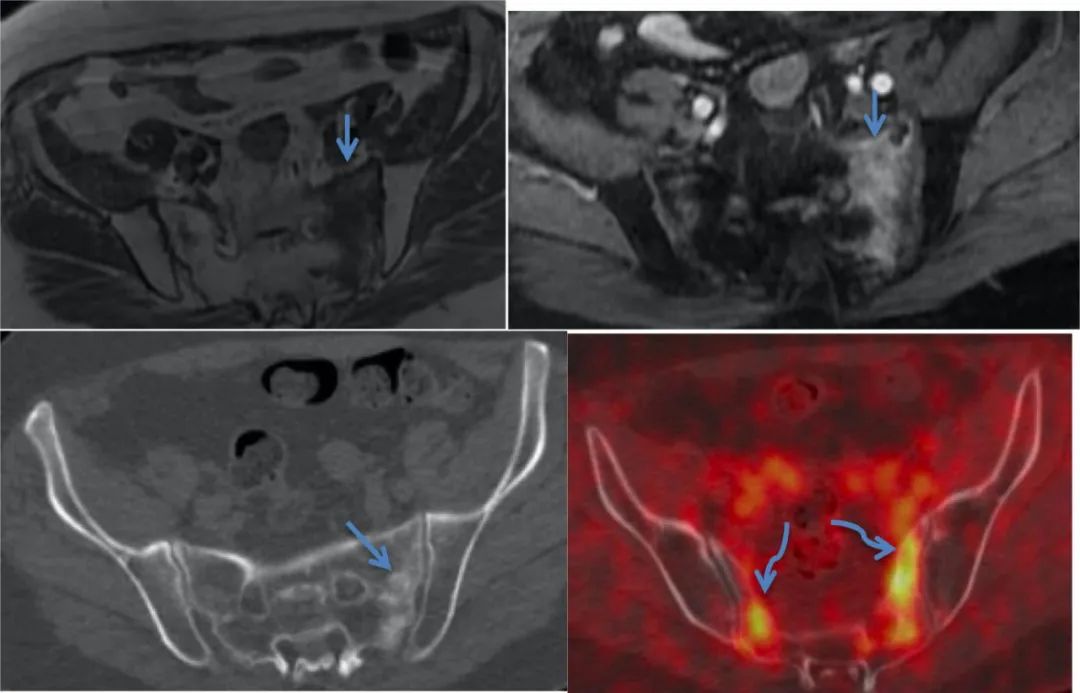

CASE 3

图 4 Case 3. MR T1WI 及增强扫描显示骶骨左侧份高信号(蓝色直箭头);FDG-PET/CT 显示双侧骶骨翼对称性摄取 FDG(蓝色弯箭头),CT 图像示骶骨左侧份骨质硬化改变。

图 5 Case 3. 随访 CT 显示骶骨骨折呈不均匀性硬化改变,骨折线可见。随访 MRI 显示骶骨骨折处稍高信号(蓝色直箭头)。骨扫描 ECT 图像可见双侧骶骨翼及髂骨体呈 Tc-99 mMDP 浓聚。